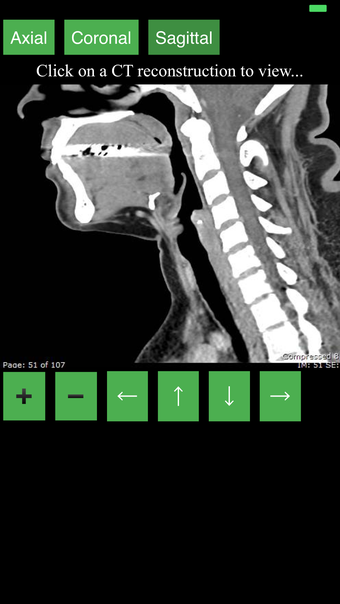

Ta aplikacja jest najwygodniejszym sposobem na przeglądanie i badanie przekrojowo anatomii człowieka na skanie CT. Może być używana jako materiał referencyjny i narzędzie edukacyjne.

Aplikacja wyświetla przekrojowy obraz tomograficzny ciała człowieka i używa systemu kodowania kolorów, aby łatwo identyfikować różne struktury tkanek miękkich i kości. Może również być używana do badania określonej części ciała, takiej jak szyja, czaszka, obręcz barkowa lub klatka piersiowa.

Użytkownik może przesuwać obraz i powiększać go, aby lepiej zidentyfikować struktury i powiększyć obraz do dalszych badań.